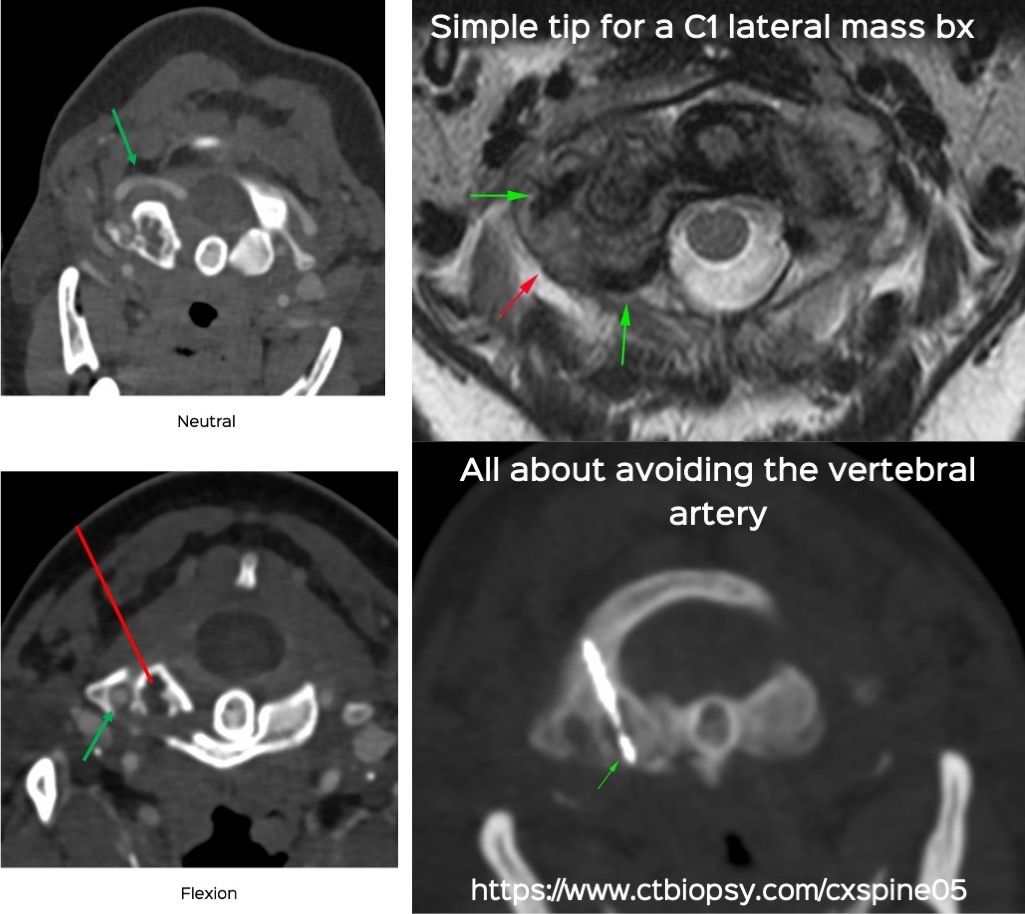

Case 72: A Tip to Simplify a C1 Lateral Mass Biopsy

Bhavin Jankharia - 24 December 2021